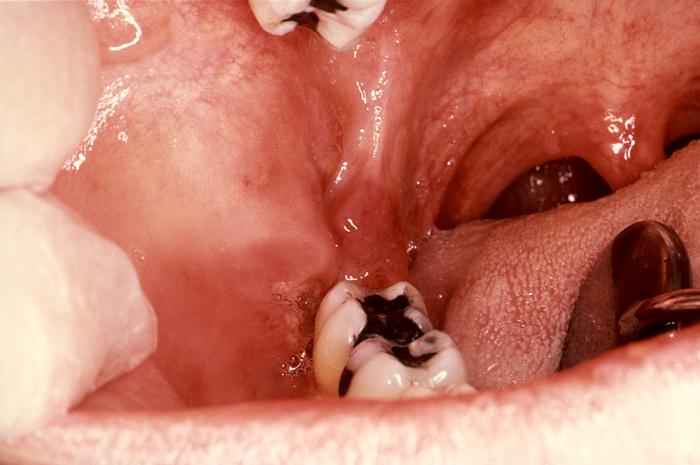

Sarcom de Kaposi en zona de trígono retromolar

El sarcoma Kaposi es la neoplasia intraoral más común que se observa en el SIDA y generalmente se presenta en el paladar duro, encías y zona del trígono retromolar, como una mancha violácea o rojiza, de límite difuso, indolora, que en el 20% de los casos puede ser la primera manifestación.

Esta neoplasia a veces presenta un aspecto tumoral, pero muchas veces se observa como una mácula rojiza, en el primer caso tiene un peor pronóstico.